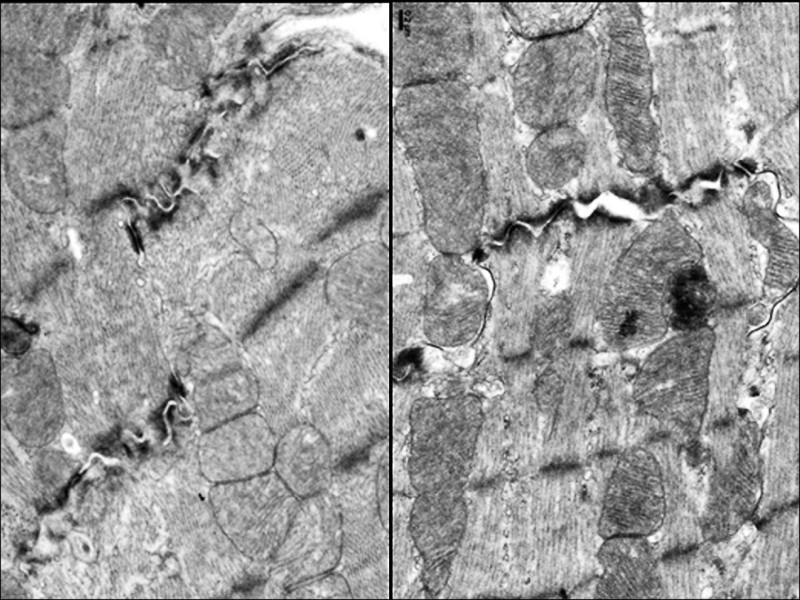

「小紅莓」化療藥是治療乳癌、淋巴癌、血癌、卵巢癌的常見用藥,臨床使用超過50年,但其心臟毒性讓病人承受心臟功能衰竭的風險。陽明交通大學生命科學系暨基因體科學研究所特聘教授蔡亭芬與傳統醫藥研究所教授傅淑玲、國家衛生研究院、林口長庚醫院共同組成的研究團隊發現,小紅莓會抑制心肌細胞中長壽基因CISD2的表現,使粒線體與鈣離子調控失衡,導致心臟收縮與節律出現問題,但橙皮素可重新啟動長壽基因CISD2,減少心肌細胞受損,撐起心臟保護傘。

而在動物實驗中,小紅莓處理的長腫瘤小鼠在注射橙皮素後,顯著改善心臟功能,腫瘤體積也明顯縮小。研究團隊並運用由美國史丹福大學提供的人類誘導性多能幹細胞(iPSC)衍生的心肌細胞加以驗證,強化支持橙皮素臨床應用的潛力。